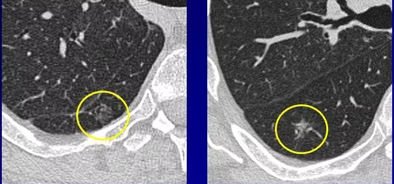

磨玻璃结节是一种在肺部CT扫描中呈现为磨玻璃样影像的结节。它的名称源于其在X光片上的表现,类似于磨砂玻璃的外观。磨玻璃结节可以是良性的,也可以是恶性的,因此不能简单地将其视为癌症的标志。

磨玻璃结节,这个名字来源于其在CT扫描中的外观,就像磨砂玻璃一样,让血管和支气管的轮廓在肺部模糊可见。这种结节的特点是肺内密度轻微增加,仿佛是一团轻柔的云雾。

纯磨玻璃结节和混杂性磨玻璃结节的主要区别在于实性成分的比例。纯磨玻璃结节在CT扫描中几乎不显示任何实性成分,或者实性成分不超过5%。而混杂性磨玻璃结节则包含更多的实性成分,这使得它们在CT扫描中更容易被识别。

在医学的诊断舞台上,肺部结节的形态特征宛如角色的脸谱,为医生提供了判断其性质的重要线索。肺部结节有多种形态,一般医生根据这些形态来协助判断结节的性质,常见的肺部结节形态有分叶、毛刺、空泡、支气管截断、胸膜凹陷、强化程度。

2. 毛刺:想象一下,如果结节边缘长出了尖锐的小刺,这种“毛刺”状结构通常是恶性的标志,因为它们好似癌细胞的侵略性生长。